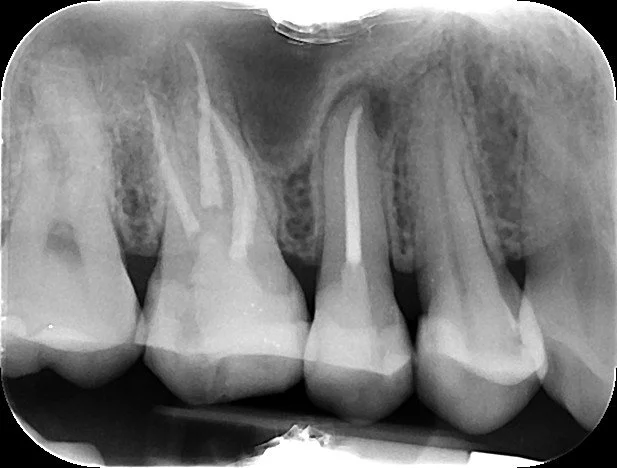

Endodontics